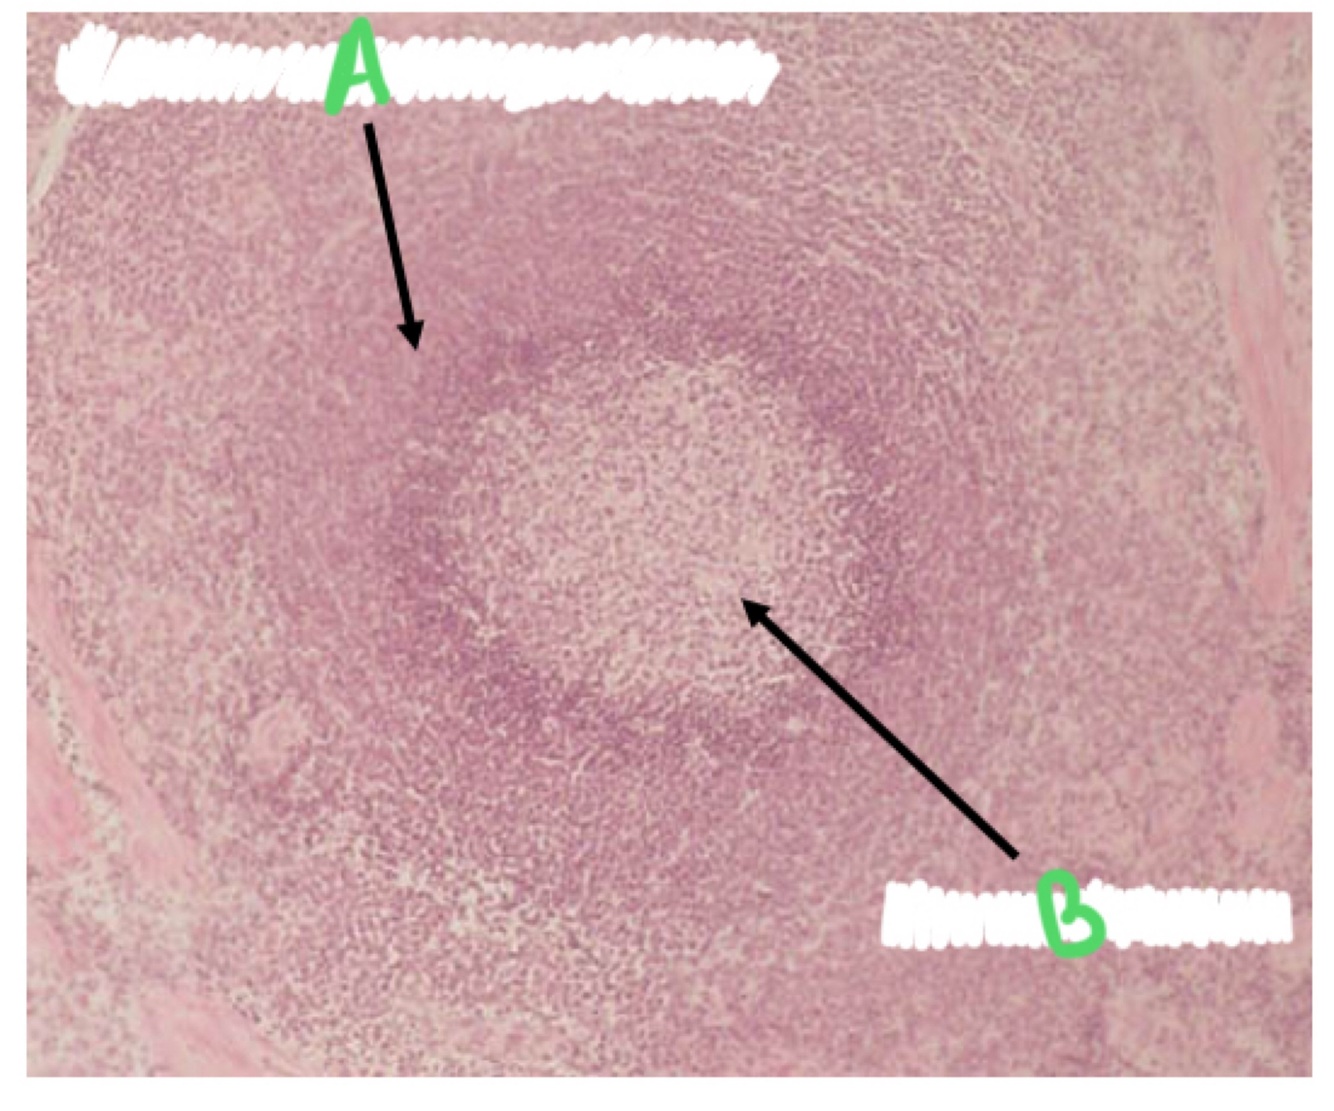

What 2 types of pulp are in the spleen?

Red pulp

White pulp

What does the white pulp contain?

Mainly contains lymphocytes

What percentage of the spleen is made up of red pulp?

80%

What separates the white and red pulp?

Marginal zone

What site in the spleen acts as a site of lymphocyte production?

Germinal centre